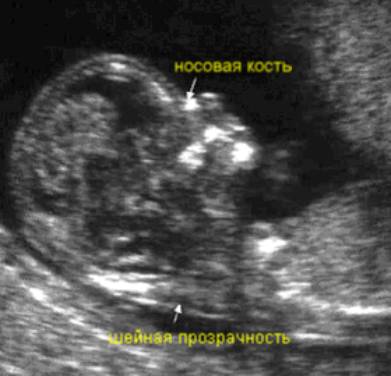

УЗ-исследование на 11 – 13 неделе беременности называется генетическим УЗИ. Это связно с тем, что на этом сроке беременности можно определить отсутствие или маленькие размеры носовой кости у плода – характерные признаки синдрома Дауна.

Рис. 7.4.7. Изображение 3D УЗИ. Присутствие носовой кости свидетельствует об отсутствии СД